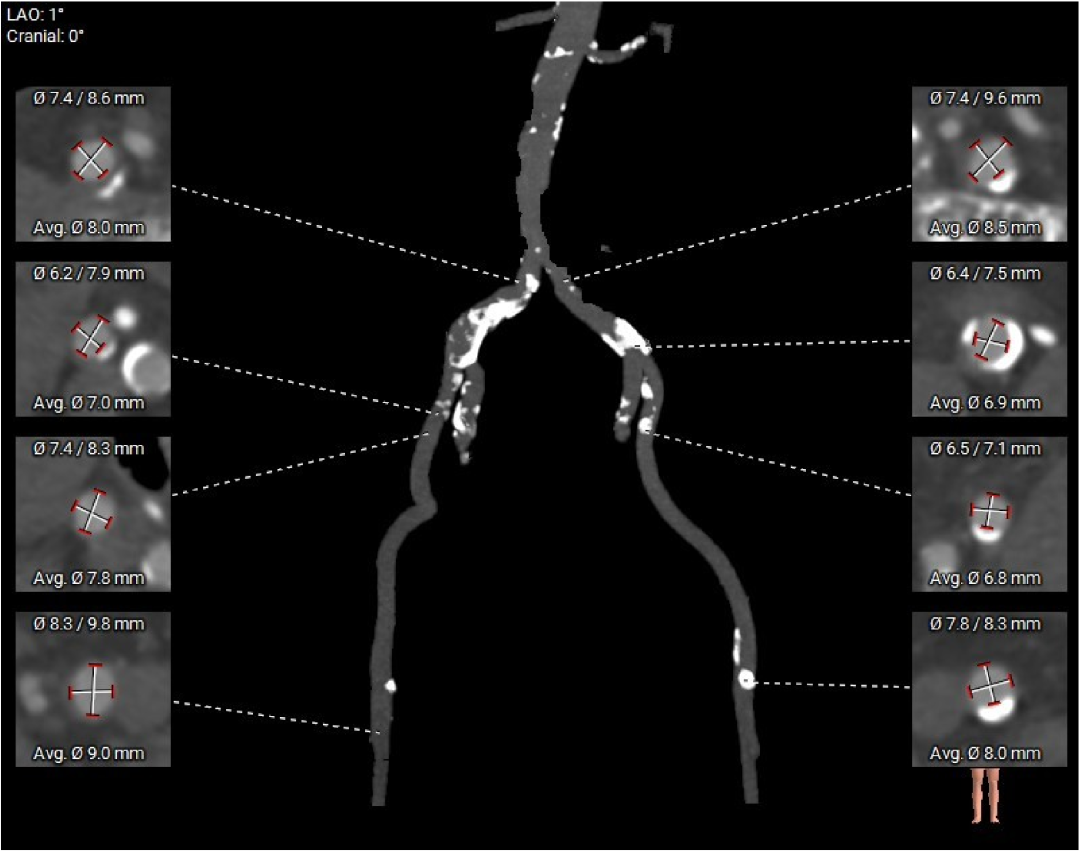

术前评估越细,术中把握才越稳

进一步评估显示,患者瓣膜狭窄程度重,瓣叶钙化明显,左心室腔径偏小,手术中对器械通过、瓣膜释放以及循环稳定性的要求都更高。团队结合术前影像和整体身体状况,制定了周密的介入治疗方案,并做好相关风险预案。

CT评估

瓣膜评估

手术过程